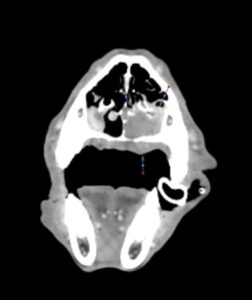

A los 18 meses del diagnóstico, los cuidadores refieren la aparición de hifema y exoftalmia en el ojo derecho, lo que sugiere metástasis, además de una masa perianal compatible con neoplasia indiferenciada (posible melanoma amelanótico). En el estudio de TC se documenta una respuesta completa de la lesión primaria y metástasis nodales y una remisión casi completa de las metástasis pulmonares (lesiones milimétricas equívocas) (imagen 1). Se realiza la resección de la masa perianal, pero los cuidadores rechazan la enucleación.

A los 28 meses se realiza un TC de re-estadiaje antes de considerar el segundo protocolo de radioterapia, donde se documenta una progresión objetiva de la masa oral y ligera progresión de la metástasis pulmonar (imagen 1).